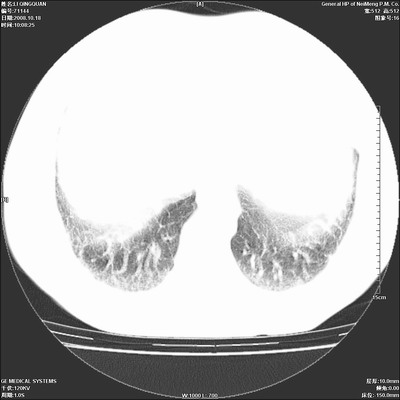

以下是引用duguo在2008-10-19 13:59:00的发言:[br]左肺上叶支气管狭窄,首先考虑中心型肺癌伴阻塞性肺炎\\肺不张.

以下是引用ybing在2008-10-19 12:58:00的发言:[br]左肺上叶阻塞性炎症-建议支气管镜进一步检查除外中央型肺癌

以下是引用随光逐影在2008-10-19 14:31:00的发言:[br]考虑左肺中央型肺癌并左肺上叶阻塞性肺炎,肺不张。